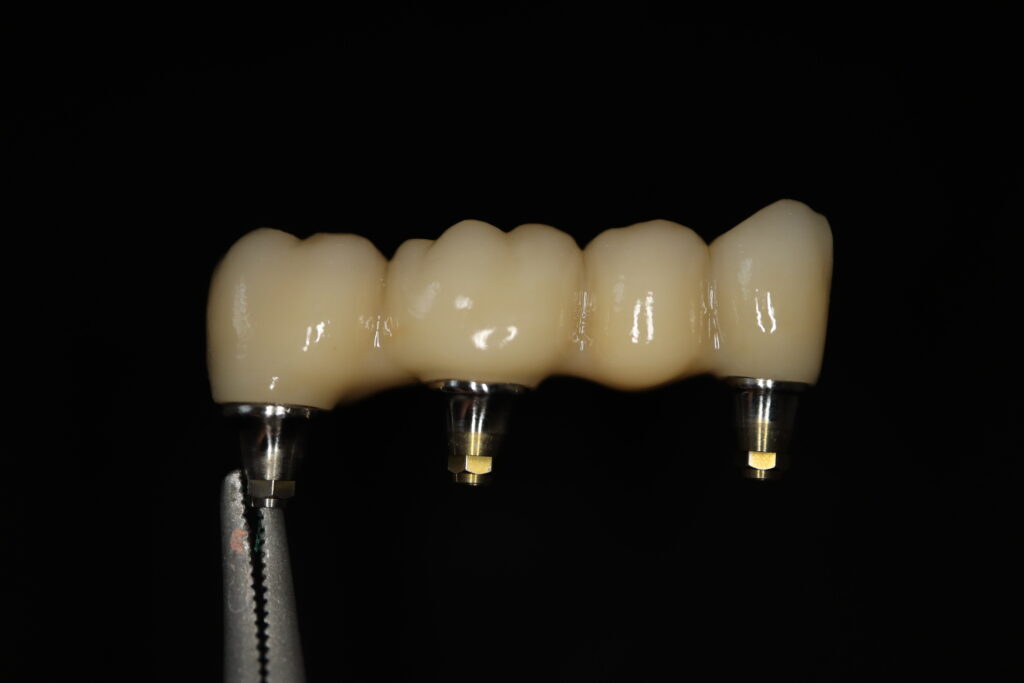

Также на нижнюю челюсть был изготовлен мостовидный протез из 4х коронок (цирконий) с опорой на 3 индивидуальных абатмента с одной стороны и 1 коронка на иплантат с другой.